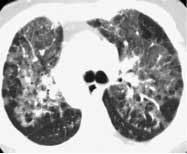

风湿性疾病肺受累常见影像学表现

非特异性

普通

急性间质性

淋巴细胞间质性

脱屑性

COP

类风湿结节